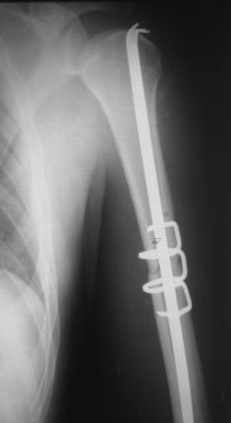

Re: Перелом плеча

Приложение как пример.